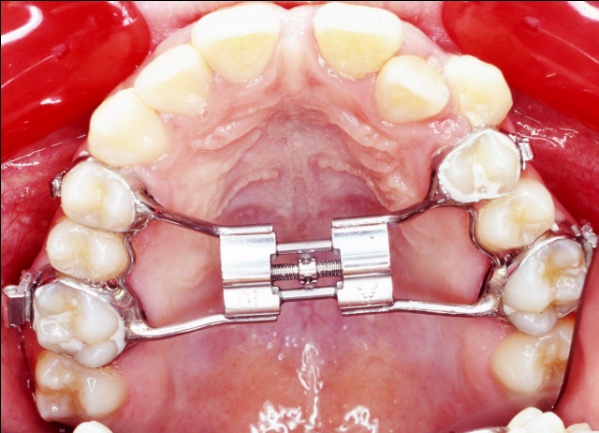

2 - Appareillage utilisé : expansion palatine et multiattaches

Cette étape montre l’utilisation d’un disjoncteur palatin pour élargir le maxillaire. Contrairement à la mandibule, le palais présente une suture médiane, véritable joint de croissance, que l’on peut activer chez l’enfant ou l’adolescent. En écartant progressivement les deux moitiés du maxillaire, on crée un gain d’espace réel, non dentaire. Cela permet de rétablir une largeur d’arcade suffisante, sans extraction, en amont de l’alignement multiattaches.